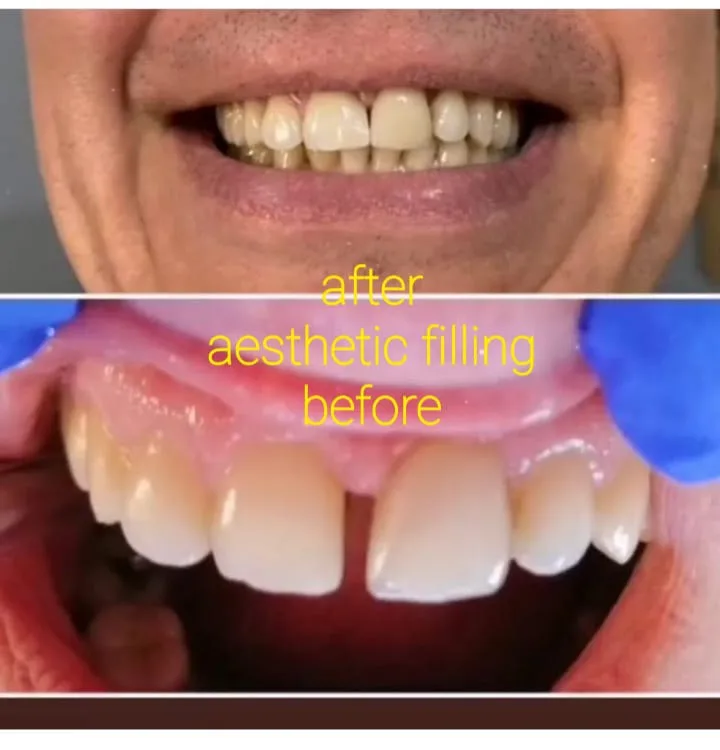

✅ 심미 치과: 미백 및 복원